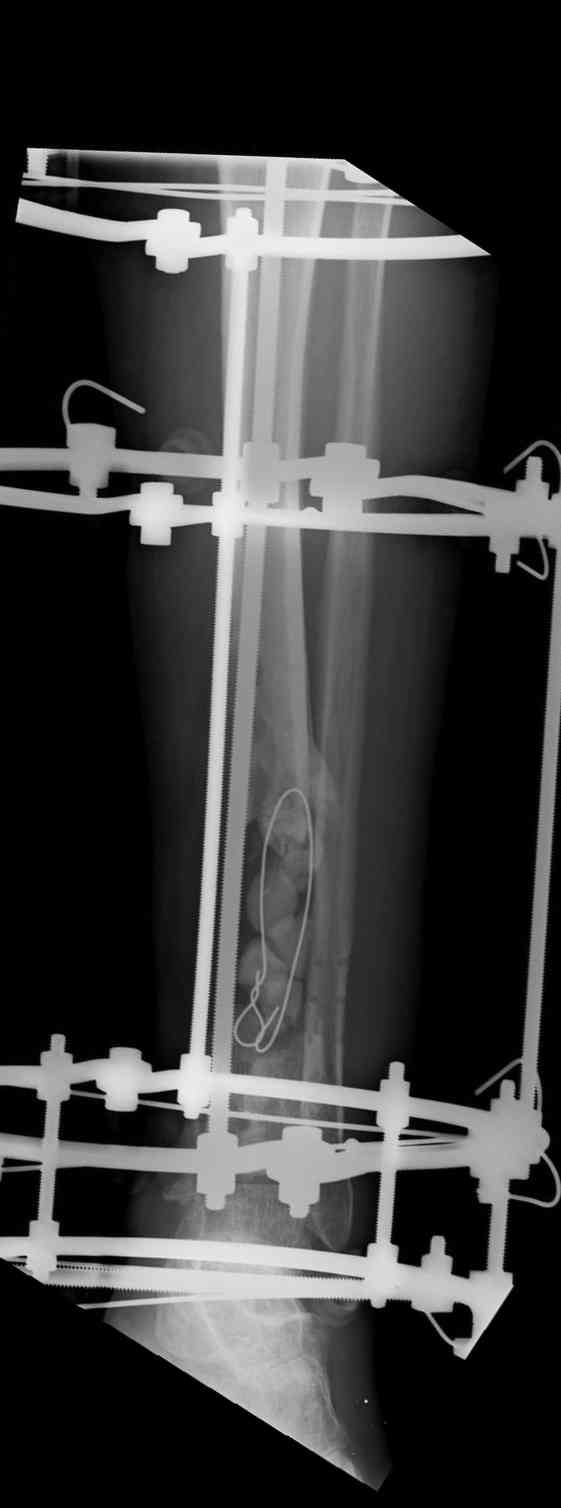

Владимир, свободная костная пластика на фоне свища вряд ли оправдана. Почему не рассматриваете вариант транспорта кости по Илизарову? Что собираетесь делать с латентной инфекцией? Одни антибиотики не помогут, необходима полноценная хирургическая обработка, Мы бы подумали о цементном спейсере с антибиотиками, бусах. После купирования инфекции переходить к замещению

дефекта: за счет удлинения концов б\б кости или тибиализации м\б. На начальном этапе фиксация только в аппарате, в последствие для удержания достигнутого можно перейти на фиксацию интрамедуллярным штифтом (см. вложенные файлы)

Как дополнение высылаю снимки и фото конечности, чтобы Вы могли оценить состояние м/т, и течение заболевания.